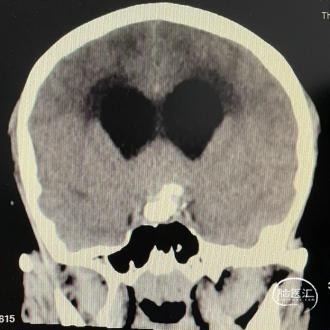

头部CT平扫显示:全鞍型蝶窦,鞍区-鞍上区-第三脑室可见一混杂密度肿块,内可见多发钙化灶,最大层面大小约43mm*35mm(左右径-前后径),CT值30HU,双侧脑室明显扩张,室旁可见对称性条片状低密度灶。